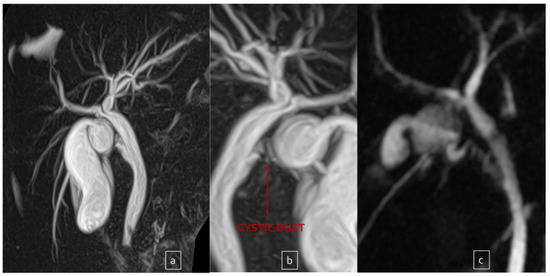

| Cholangio-MRI | Dysmorphic inflamed gallbladder with tiny infundibulum and convoluted cystic duct | Presence of gallstones | Anomaly in the biliary tract anatomy: cystic duct projected into an aberrant right anterior hepatic duct | Presence of gallstones | Presence of gallstones |